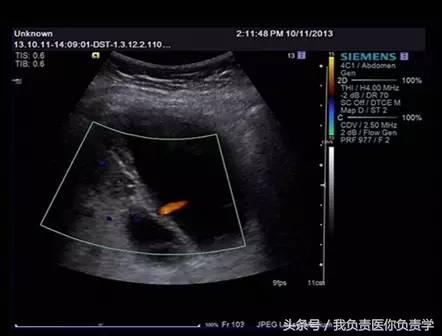

患者女,68岁,因上腹部痛 8天就诊 。超声检查发现胆囊体积明显增大,内部透声差,囊壁明显增厚,胆囊周围可见不规则分布的液性暗区。胆囊壁局部回声中断,探头加压及松开时,CDFI可见中断处出现因液体进出胆囊而导致的多普勒信号。患者行胆囊切除术,术后证实为胆囊穿孔。

图1示胆囊体积明显增大,内部透声差

图2示胆囊周围可见液性暗区分布

图3-图6示胆囊壁局部回声中断,探头加压及松开时CDFI可见红色及蓝色多普勒信号